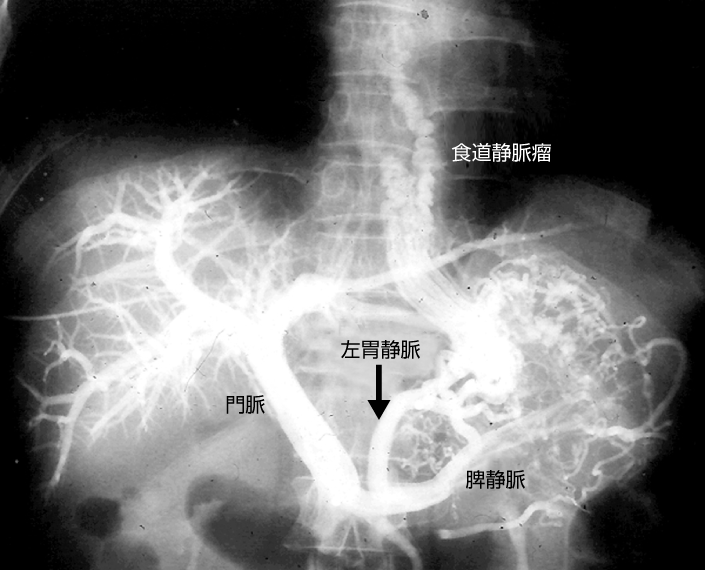

経皮経肝門脈造影

門脈および供血路、食道静脈瘤が描出されている。